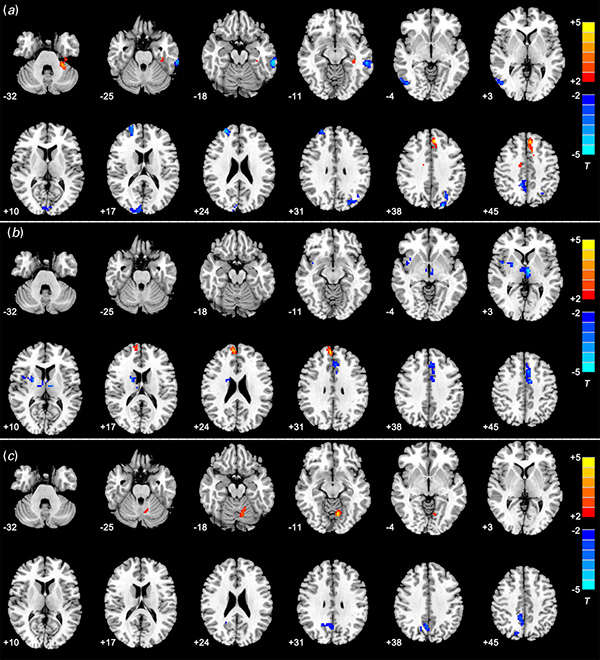

图:背尾壳核的静息态功能连接的组间差异

Wang L, Li F, Mitchell P B, et al. Striatal Resting-State Connectivity Abnormalities Associated With Different Clinical Stages of Major Depressive Disorder[J]. The Journal of clinical psychiatry, 2020, 81(2): 0-0.